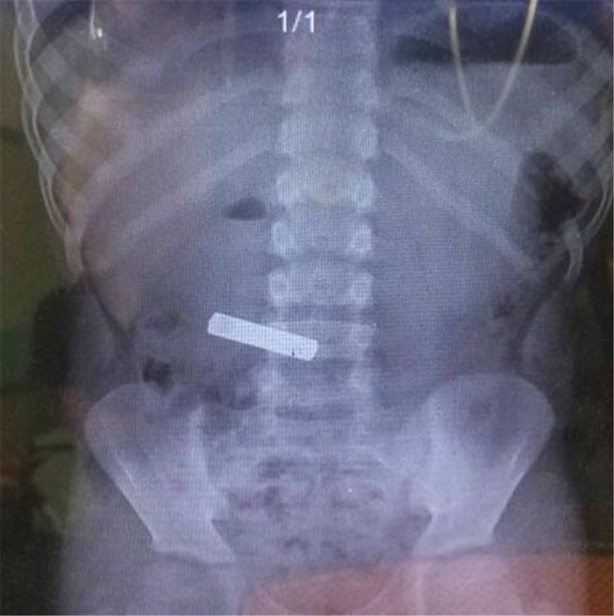

İzmir Tepecik Eğitim ve Araştırma Hastanesi Çocuk Gastroenteroloji Bölümü'nün, yabancı cisim yutan çocukların nefes ve borusu ile midelerinden çıkarttığı, anahtarlık, madeni para, saat pili, ataç, çengelli iğne ve çivi gibi objeler görenleri hayrete düşürdü.

Bu objelerden en tehlikelisinin piller olduğuna dikkat çeken Doç.Dr. Maşallah Baran, "Piller kimyasal mekanizmayla mukozayı yakıyor, özellikle yemek borusu çok duyarlı pillere, hele ki yeni takılmış bir pilse saatler içinde şahit olduğum bir kaç vaka var, yemek borusunu kömür haline getirebiliyor" dedi.